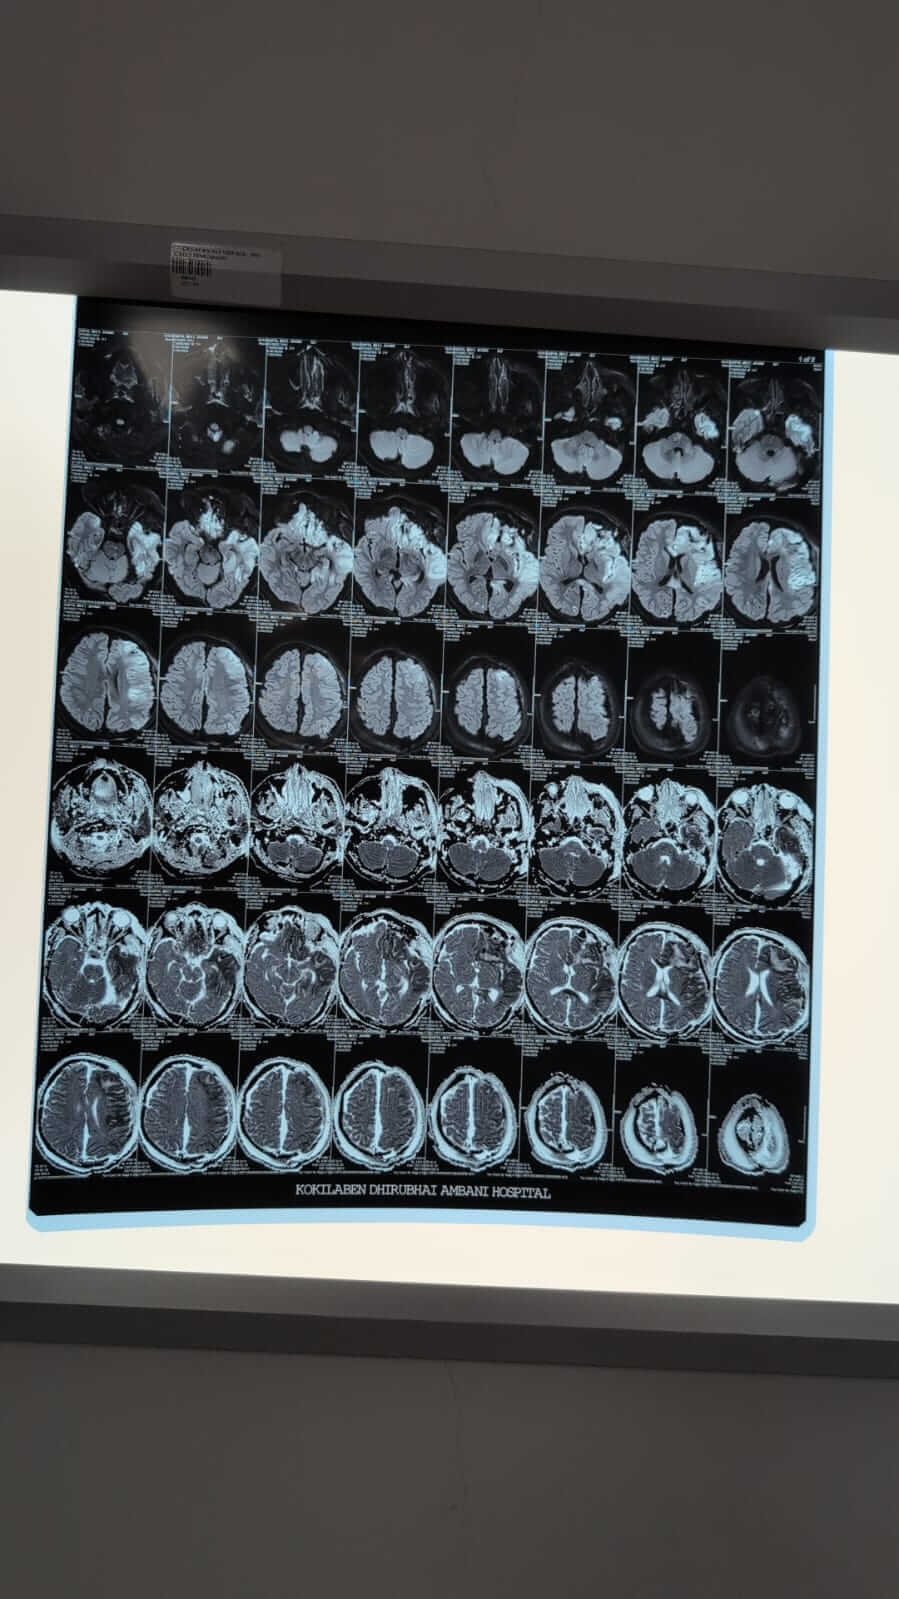

I still can’t process how one normal day turned into this. My brother Meet was just coming back home from college, and then one phone call changed everything. They said he fell from a moving train at Andheri. When I saw him in the hospital, he didn’t look like the same person. His head was badly injured, and doctors had to rush him for brain surgery to control the swelling and remove a blood clot.

Those hours felt endless. Even now, he hasn’t opened his eyes yet, but I hold onto every small sign, the way his fingers move, the slight movement in his legs, his lips trying to say something. He’s breathing on his own now, and the doctors say the swelling has reduced, but he still has a long way to go.

They’ve shifted him to rehabilitation, and the next 2–3 months are critical. Every single day, he needs constant care, different therapies, and strong medication just to help his body remember how to function again.